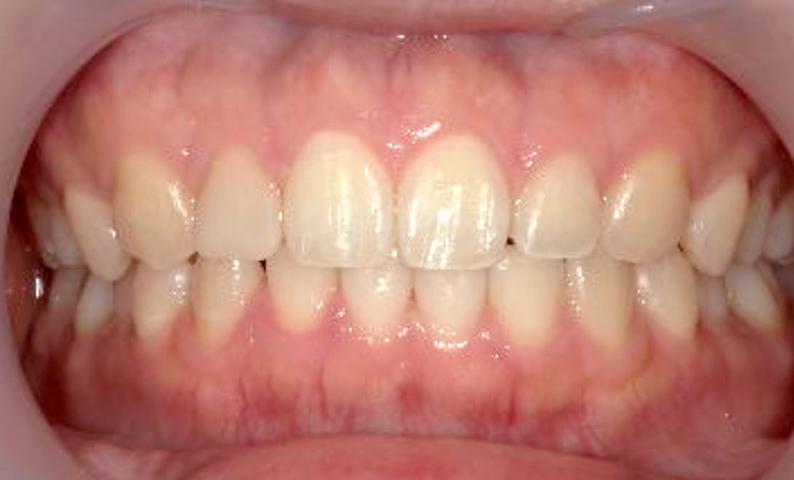

| 治療前 | 治療後 |

|---|---|

|